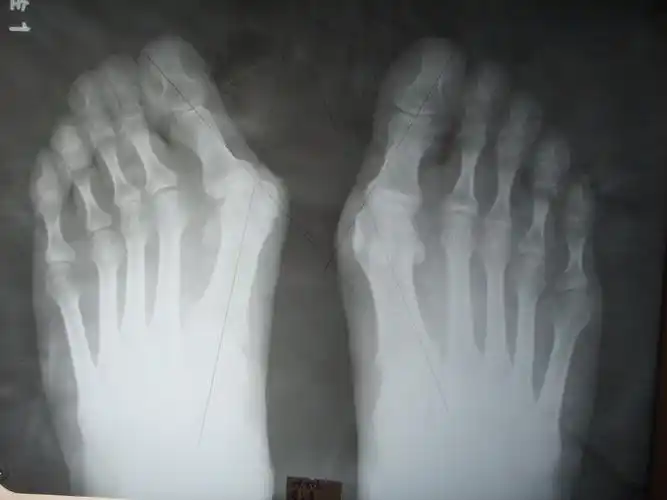

36岁双足拇外翻畸形矫正手术一例

脚骨x光片术前术后对比在油管上查了很多关于拇外翻手术的视频(血腥

负重x线片观察:第一二跖骨间夹角增大明显,第二跖趾关节半脱位.